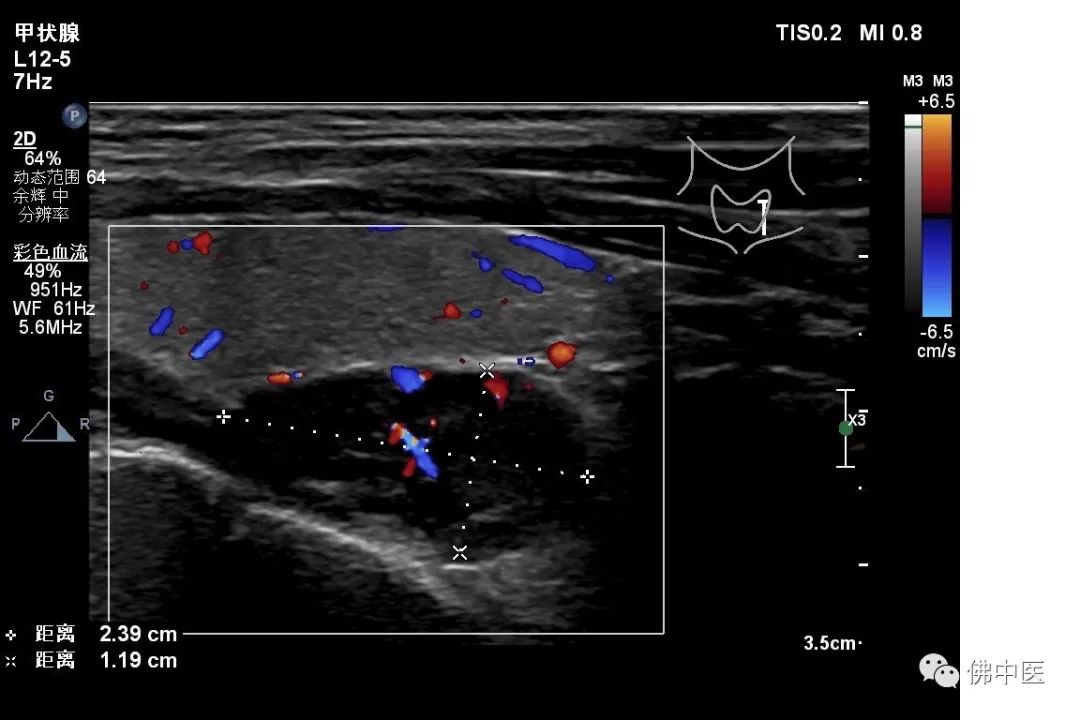

两名患者入院后住院生化检查提示碱性磷酸酶明显升高,血钙升高,但血磷下降,呈钙磷倒置现象,但肿瘤指标均未见明显异常;骨密度检查均提示“骨质疏松”;胸与双肺、全腹平扫+增强CT检查未见明显异常。针对此种具有恶性肿瘤征象,但无明确恶性肿瘤证据的患者,骨病专科主任劳永锵教授建议完善甲状腺彩超检查及甲状旁腺激素测定,结果两例患者甲状旁腺激素均明显升高,甲状腺彩超检查均可发现实性结节。

基于此种临床特点,劳永锵教授组织主管医生胡永波、潘海文请我院普通外科为两名患者进行会诊,普通外科霍景山博士详细诊查了两名患者,考虑他们为:“甲状旁腺功能亢进并甲状旁腺瘤”,建议转普通外科行手术治疗。

病例一(甲状腺彩超)